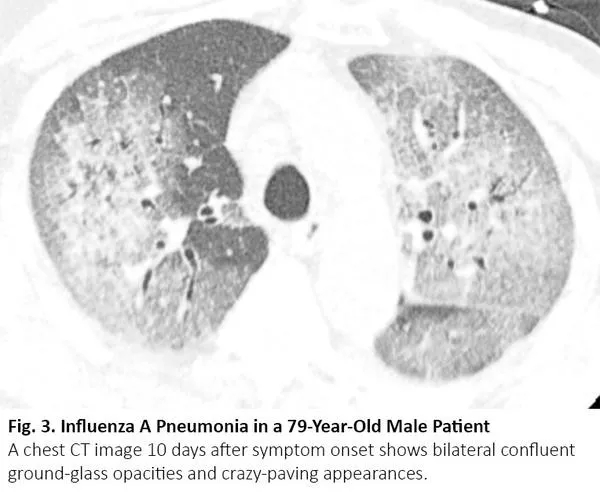

吸烟增加罹患肺癌和特发性肺纤维化(IPF)的风险,特发性肺纤维化患者罹患肺癌的风险会增加。当患者接受手术或放疗时,若特发性肺纤维化急性加重,CT可呈现双肺弥漫性或外周磨玻璃影,17与COVID-19肺炎相同(图7)。

图7. 一位72岁的小细胞肺癌女性患者出现特发性肺纤维化急性加重